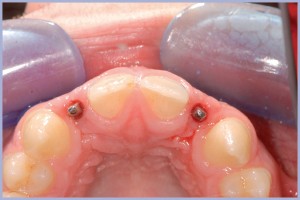

- Figg. 6, 7 – Prova dei monconi in titanio

- Fig. 7